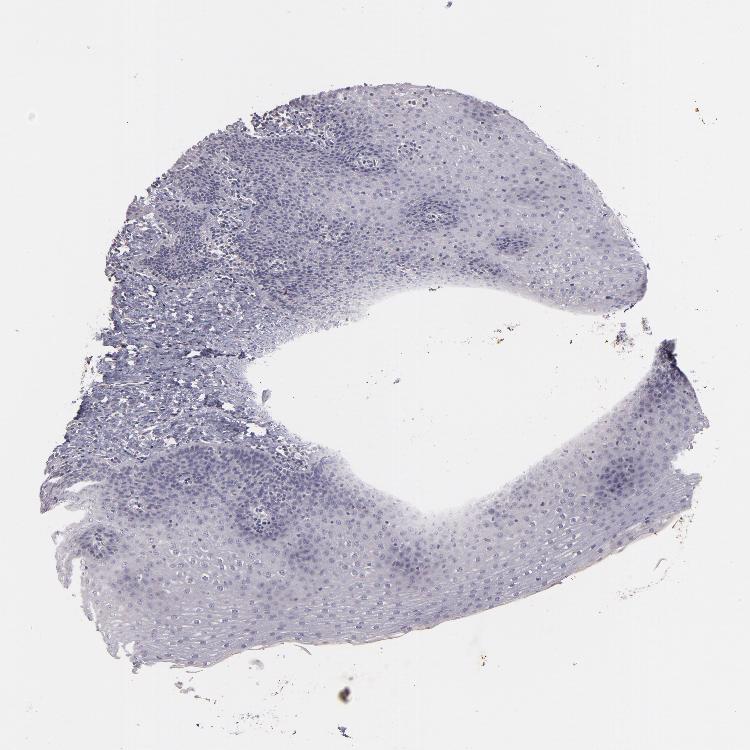

ESOPHAGUS - Antibody stainingi

Antibody staining in the annotated cell types in the current human tissue is reported as not detected, low, medium, or high, based on conventional immunohistochemistry profiling in selected tissues. This score is based on the combination of the staining intensity and fraction of stained cells.

Each image is clickable and will lead to virtual microscopy that enables deeper exploration of all samples and also displays staining intensity scores, fraction scores and subcellular localization as well as patient and tissue information for each sample.

Antibody HPA035876Antibody CAB002681

Squamous epithelial cells Not detectedNot detected